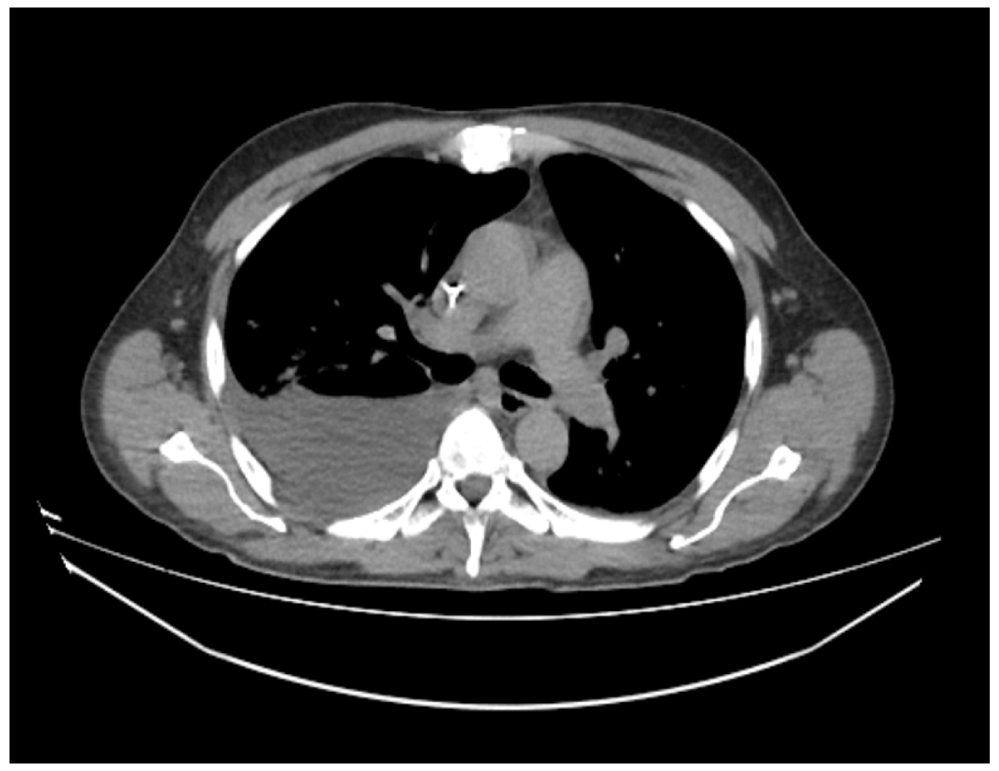

On the 19th day of illness, a non-enhanced computed tomography (CT) of the chest and abdomen was conducted because the patient’s condition had not improved despite the administration of various therapeutic agents, including antibacterials (levofloxacin, vancomycin, and meropenem) and human immunoglobulins. Bilateral ground-glass opacity and right-sided partial atelectases in the lower and median lobes were visualized on CT scans. The 50×72×70-mm abscesses were detected in the hepatic segment 6 (S6). A similar 61×47×65-mm lesion was found in the S5 segment. The fluid was visualized in the pelvis (up to 47 mm) and in the lesser sac (179×69 mm; Figures 1 and 2).

Fig. 2. Computed tomography of the chest.